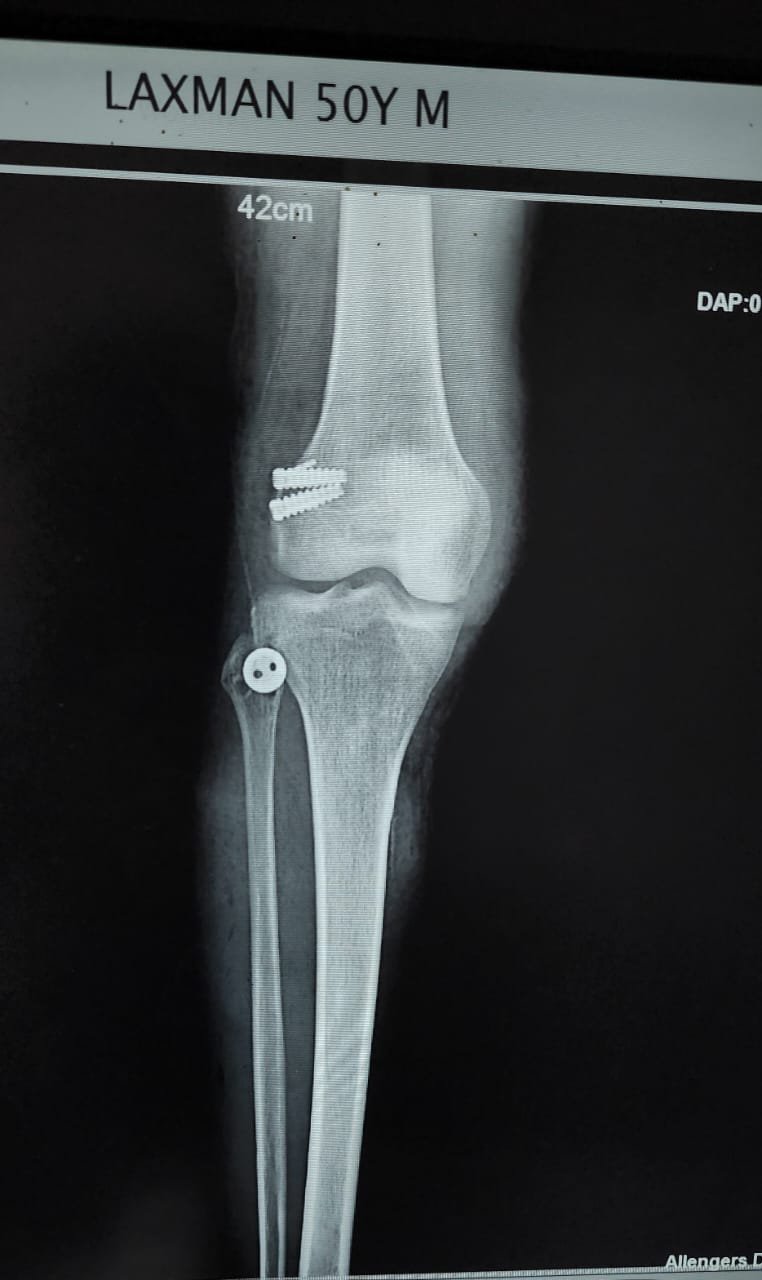

- Knee Replacement Surgery